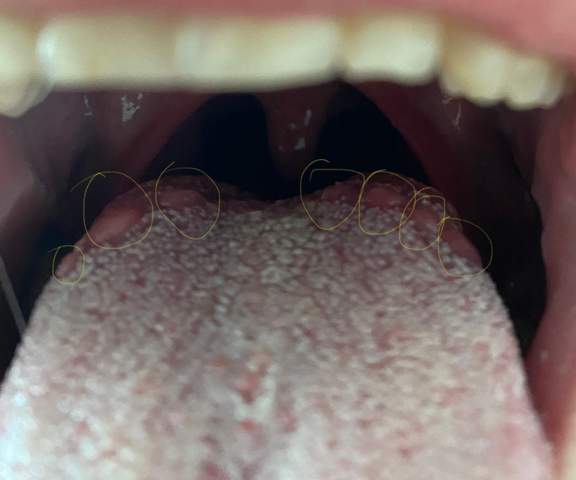

Kaffee und andere stark färbende. Ist die Zunge von einem starken weißen Belag bedeckt ist dies häufig ein Anzeichen für einen Infekt wie eine Erkältung oder Grippe. Eine leicht weiß belegte Zunge ist normal weil sich im Lauf des Tages abgestorbene Zellen verschiedenste Mikroorganismen und Speisereste auf der Zunge ansammeln.

Eine gelbe Zunge ist in den meisten Fällen harmlos. Bei einer weiß-belegten Zunge besteht der Belag typischerweise aus abgestorbenen Zellen Mikroorganismen und Nahrungsresten die sich an der rauen Zungenoberfläche absetzen.

Akute Magenschleimhautentzündung und andere Magen-Darm-Probleme. Ist die Zunge von einem starken weißen Belag bedeckt ist dies häufig ein Anzeichen für einen Infekt wie eine Erkältung oder Grippe. Flecken auf der Zunge sind fast immer weiß oder rot gefärbt können harmlos sein und auf Dehydratation hinweisen oder infolge einer Erkrankung entstehen. Bei einer weiß-belegten Zunge besteht der Belag typischerweise aus abgestorbenen Zellen Mikroorganismen und Nahrungsresten die sich an der rauen Zungenoberfläche absetzen. Kaffee und andere stark färbende. Das Vorhandensein von Leukoplakie kann auch ein Hinweis auf Krebs sein. Akute Magenschleimhautentzündung und andere Magen-Darm-Probleme. Eine differenzialdiagnostische Untersuchung ist daher erforderlich um Zungenschmerzen mit Belagbildung abzuklären. Die Ernährung hat einen Einfluss auf den Belag auf der Zunge Darüber hinaus hat auch die Ernährung einen Einfluss auf die Farbe der Schicht auf der Zunge.

Akute Magenschleimhautentzündung und andere Magen-Darm-Probleme. Eine weiße Zunge deutet auf Magen- Darmprobleme hin. Nach dem Essen bekomme ich manchmal Schmerzen und ein Zungenstechen dabei kommt dies unregelmäßig. Das Vorhandensein von Leukoplakie kann auch ein Hinweis auf Krebs sein. Dünner weißer Belag im Übergangsbereich zwischen vorderem und mittlerem Drittel der Zunge. Eine gelbe Zunge ist in den meisten Fällen harmlos. Die wirklich gelbe Zunge nicht rötlich weiß oder braun-schwarz weist auf Störungen hin die von der Leber oder der Galle ausgehen.